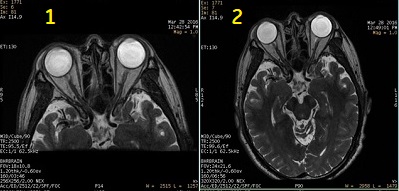

By modulating the refocusing pulses’ flip angle, the range of image contrast is expanded from conventional FSE Fast Spin Echo applications.

| Number | Description |

|---|---|

| 1 | Equivalent TE of 100 ms |

| 2 | Equivalent TE of 585 ms for hydrographic image contrast |